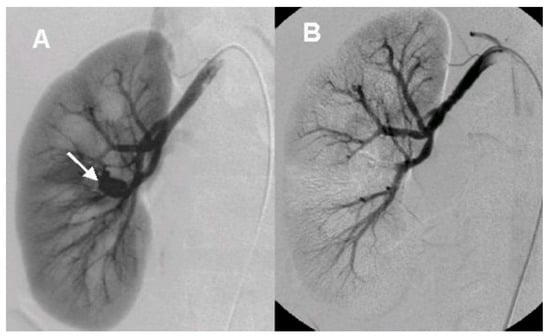

After the initial lab test and imaging study, all patients underwent diagnostic renal angiography for suspicious signs or symptoms such as persistent hematuria, flank pain, hydronephrosis, hematoma in renal pelvis, or hematuria from ureteral orifice on cystoscopy. Angiographic findings showed tortuous vascular communications or aneurysmal dilation with early venous drainage (Figure 2 and Figure 3).

Figure 3. The angiographic findings of cirsoid arteriovenous malformation (A). Renal angiography shows tangled and conglomerated vascular structure (arrow, cirsoid type) with early venous drainage (B). Embolization was performed with PVA particle (Contour, 150–250 µm).